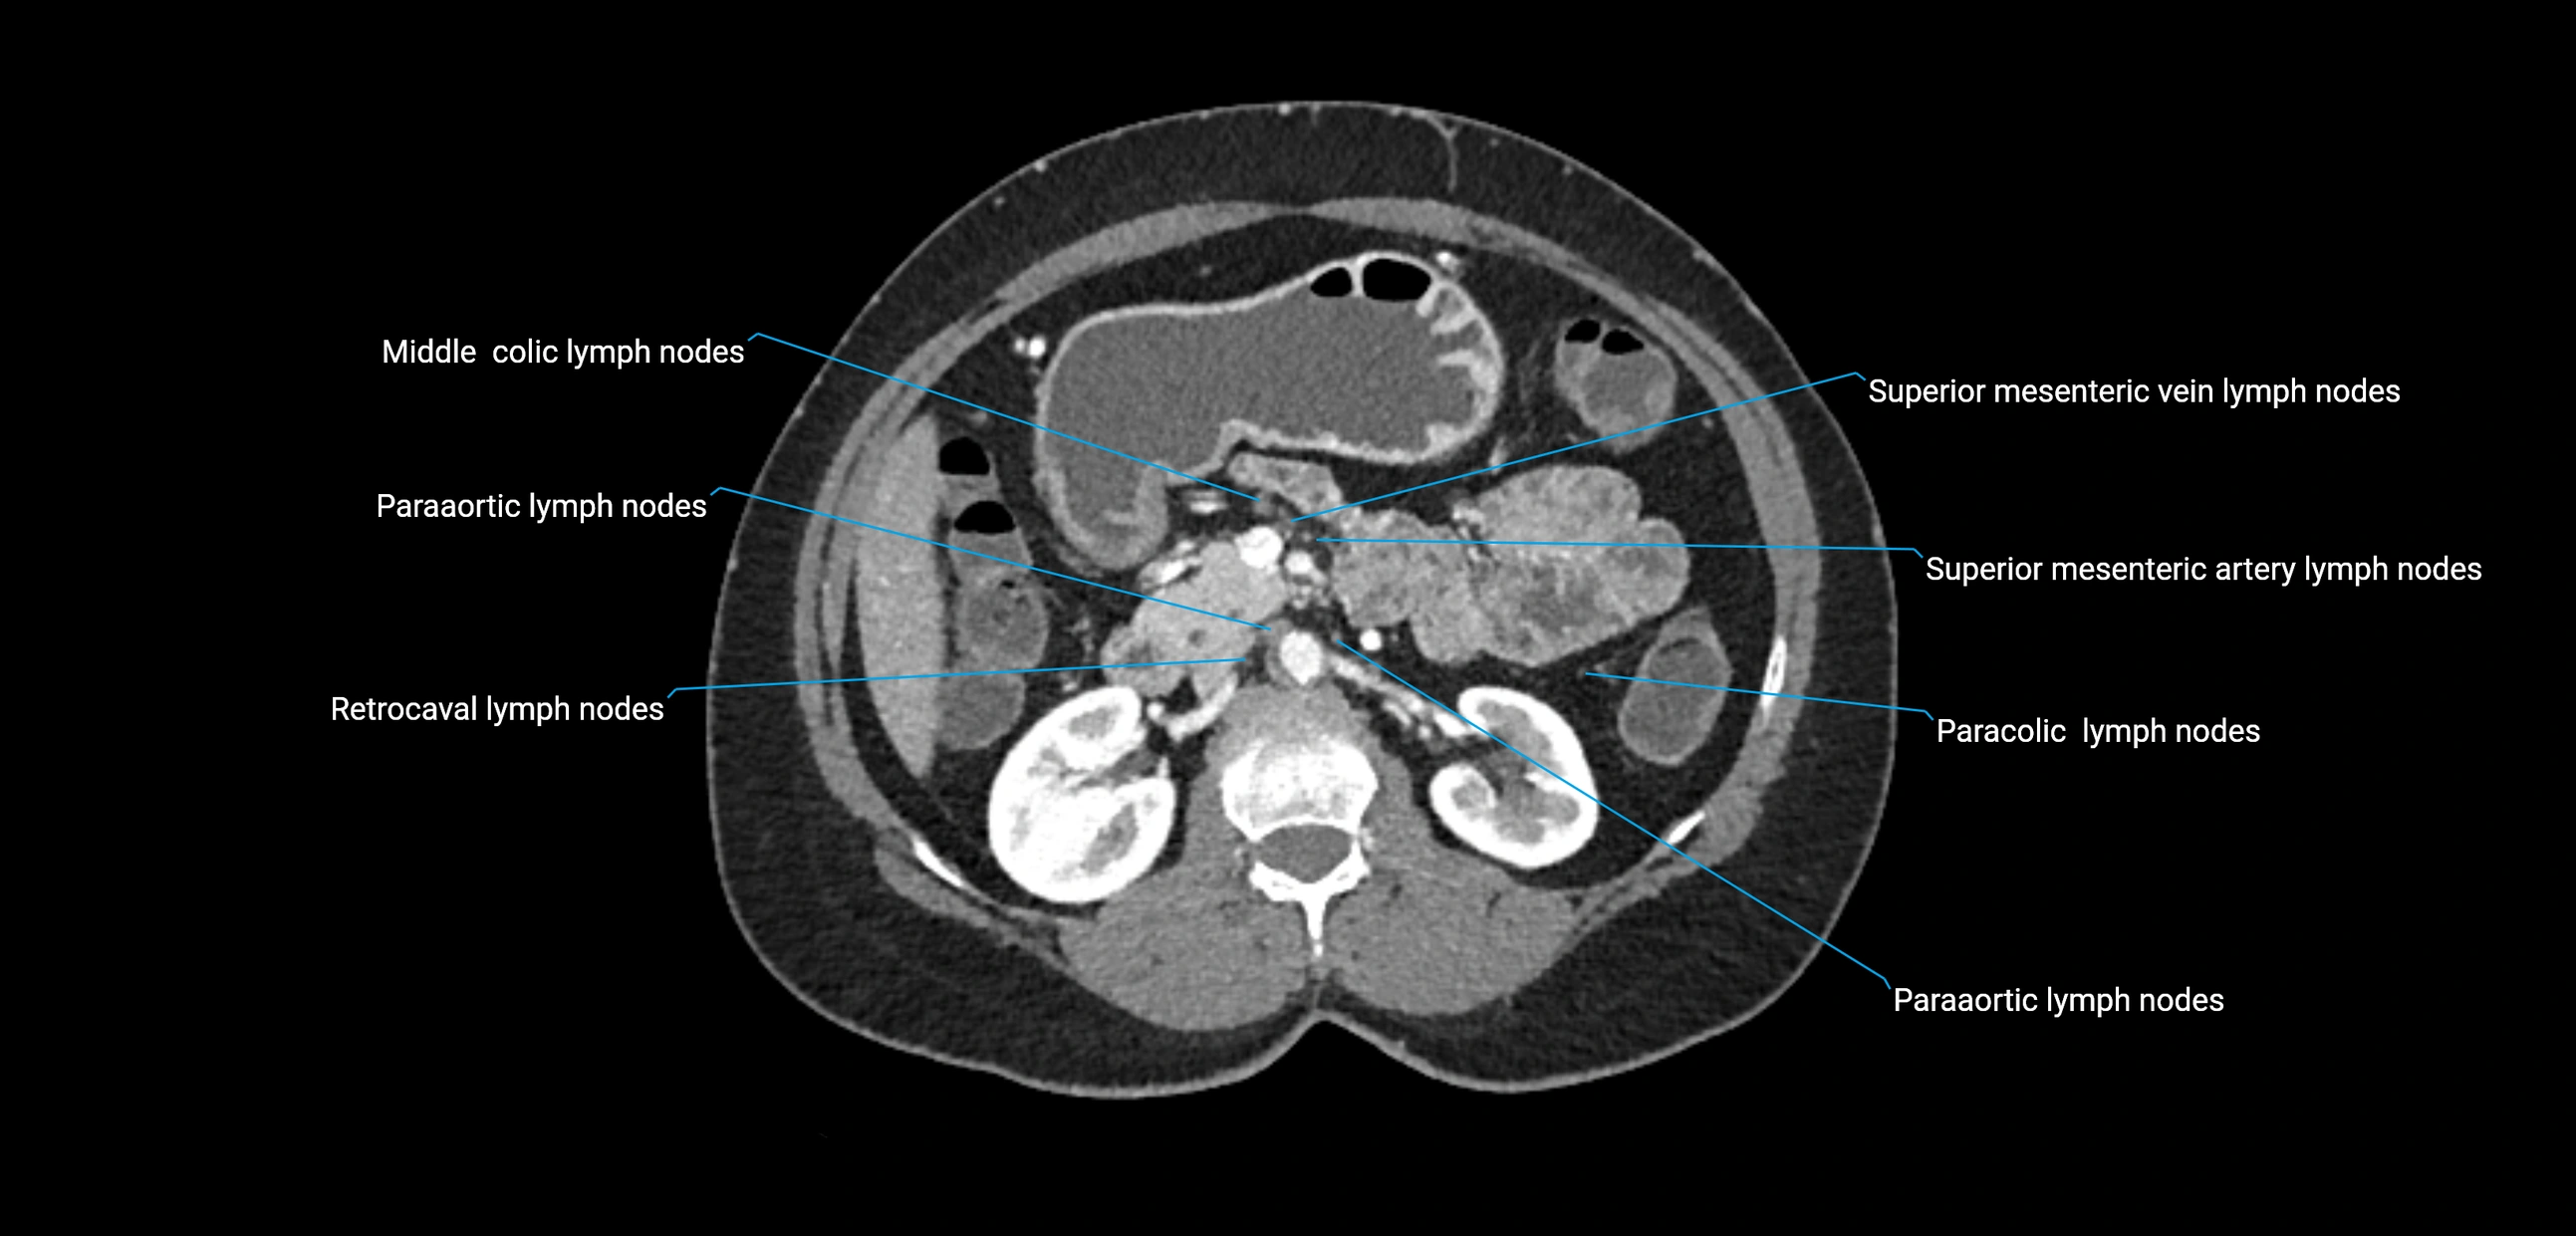

MRI images

image